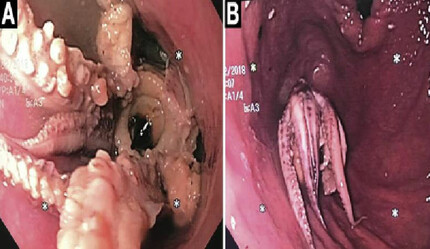

Mide bağırsak hastalıkları ile kaygı bozuklukları arasında yakın bir ilişki olduğunu aktaran Prof. Dr. Bor, bu durumun eskiden beri bilindiğini ancak son yapılan çalışmadaki yüksek oranların hekimleri şoke ettiğini aktardı. Hastanın eğer depresyonu ve kaygı bozukluğu varsa mide ve bağırsak şikâyetlerini daha ağır hissettiğini söyleyen Prof. Dr. Bor “Biz buna somatizasyon bozukluğu diyoruz. Bu kişilerde ağır hastalık olmadığı hâlde, yapılan bütün testleri temiz olmasına rağmen karın ağrısı, şişkinlik, kabızlık, geğirme, mide ağrısı gibi problemleri yoğun yaşar. Hiçbir şeyi olmadığı hâlde 20 defa endoskopi çektiren, 10 defa kolonoskopi yaptırmış hastalarım oldu. Her türlü tetkik yapıldıktan sonra fiziksel değerlendirmede bir hastalık etkeni tespit edilmemişse ve şikâyetler devam ediyorsa mutlaka bir psikiyatrik destek alınmalı” dedi.

Tıbbın yeni geliştirilen ileri endoskopik cihazlarla çok erken teşhis koyma ve hastanın hayatını kurtarma şansına sahip hâle geldiğini söylen Türk Gastroenteroloji Derneği Başkanı Prof. Dr. Mehmet Cindoruk “Daha önce kullanılan cihazlarla gelişmiş cihazlar arasındaki farkı ‘araba farları’ ve ‘projektör’ arasındaki farkla açıklayabiliriz. Projektörü yakınca erken kanserleri, erken doku kaybını, iyi ya da kötü huylu tümör olup olmadığı yönünde teşhis koyma şansı veriyor. Mesela, pankreas modelinde teşhis için endoskopik ultrason kullanıyoruz. MR veya CT’nin kaçırdığı bazı lezyonlarda endoskopik ultrasonografiyle çok erken bir teşhis koyma şansına sahibiz. 1 santimetreden daha küçük lezyonları görerek, onların kanser olup olmadığına karar verebiliyor, böylece erkenden en çok korktuğumuz pankreas kanserinde dahi ameliyat kararı alabiliyoruz. Böylece hastanın hayatını kurtarmış oluyoruz” dedi.